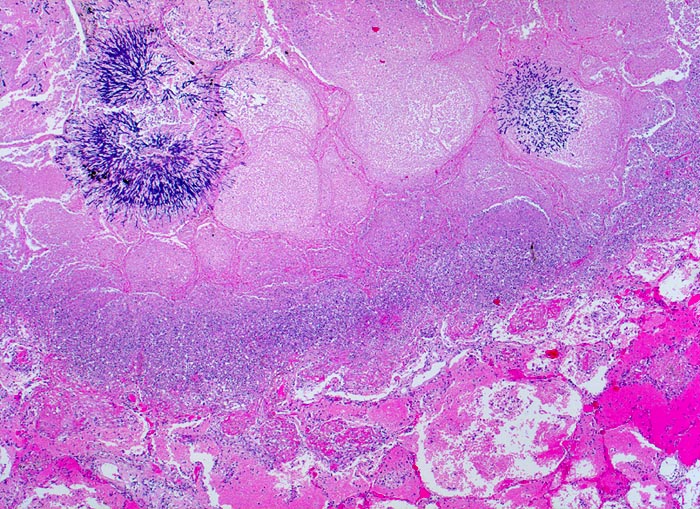

Aspergillen gehören in die Gruppe der Schimmelpilze und wachsen ubiquitär auf organischen Stoffen. Der Erreger ist charakterisiert durch echte septierte Hyphen von 3 bis 6 Mikrometer Durchmesser. Die Hyphen verzweigen sich in einem Winkel von 45 Grad. Selten sind auch die (> 10851) (> 10849) Fruchtköpfe (Conidiophoren) nachweisbar. Aspergillusinfekte manifestieren sich je nach Resistenzlage als Aspergillom, invasive Aspergillose oder allergische Aspergillose. Der Nachweis von Aspergillus beweist noch nicht eine klinisch relevante Infektion.